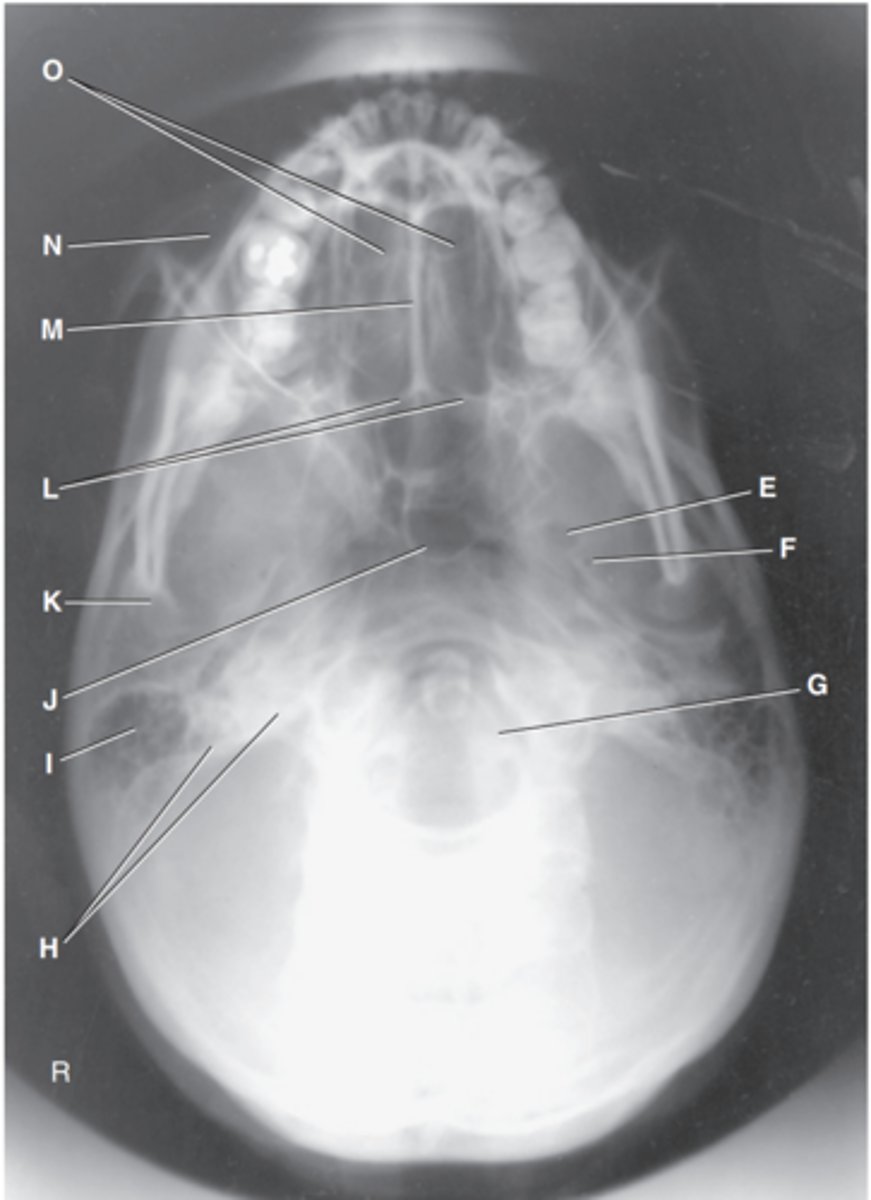

Foramen magnum

Label J

Zygomatic arch

Label A

Palatine process of maxilla

Label B

Horizontal process of palatine bone

Label C

Pterygoid hamulus of sphenoid

Label D

Foramen ovale of sphenoid

Label E

Foramen spinosum of sphenoid

Label F

Foramen magnum

Label G

Petrous pyramid of temporal bone

Label H

Mastoid portion of temporal bone

Label I

Sphenoid sinus in body of sphenoid

Label J

Condyle of mandible

Label K

Posterior border of palatine bone

Label L

Vomer

Label M